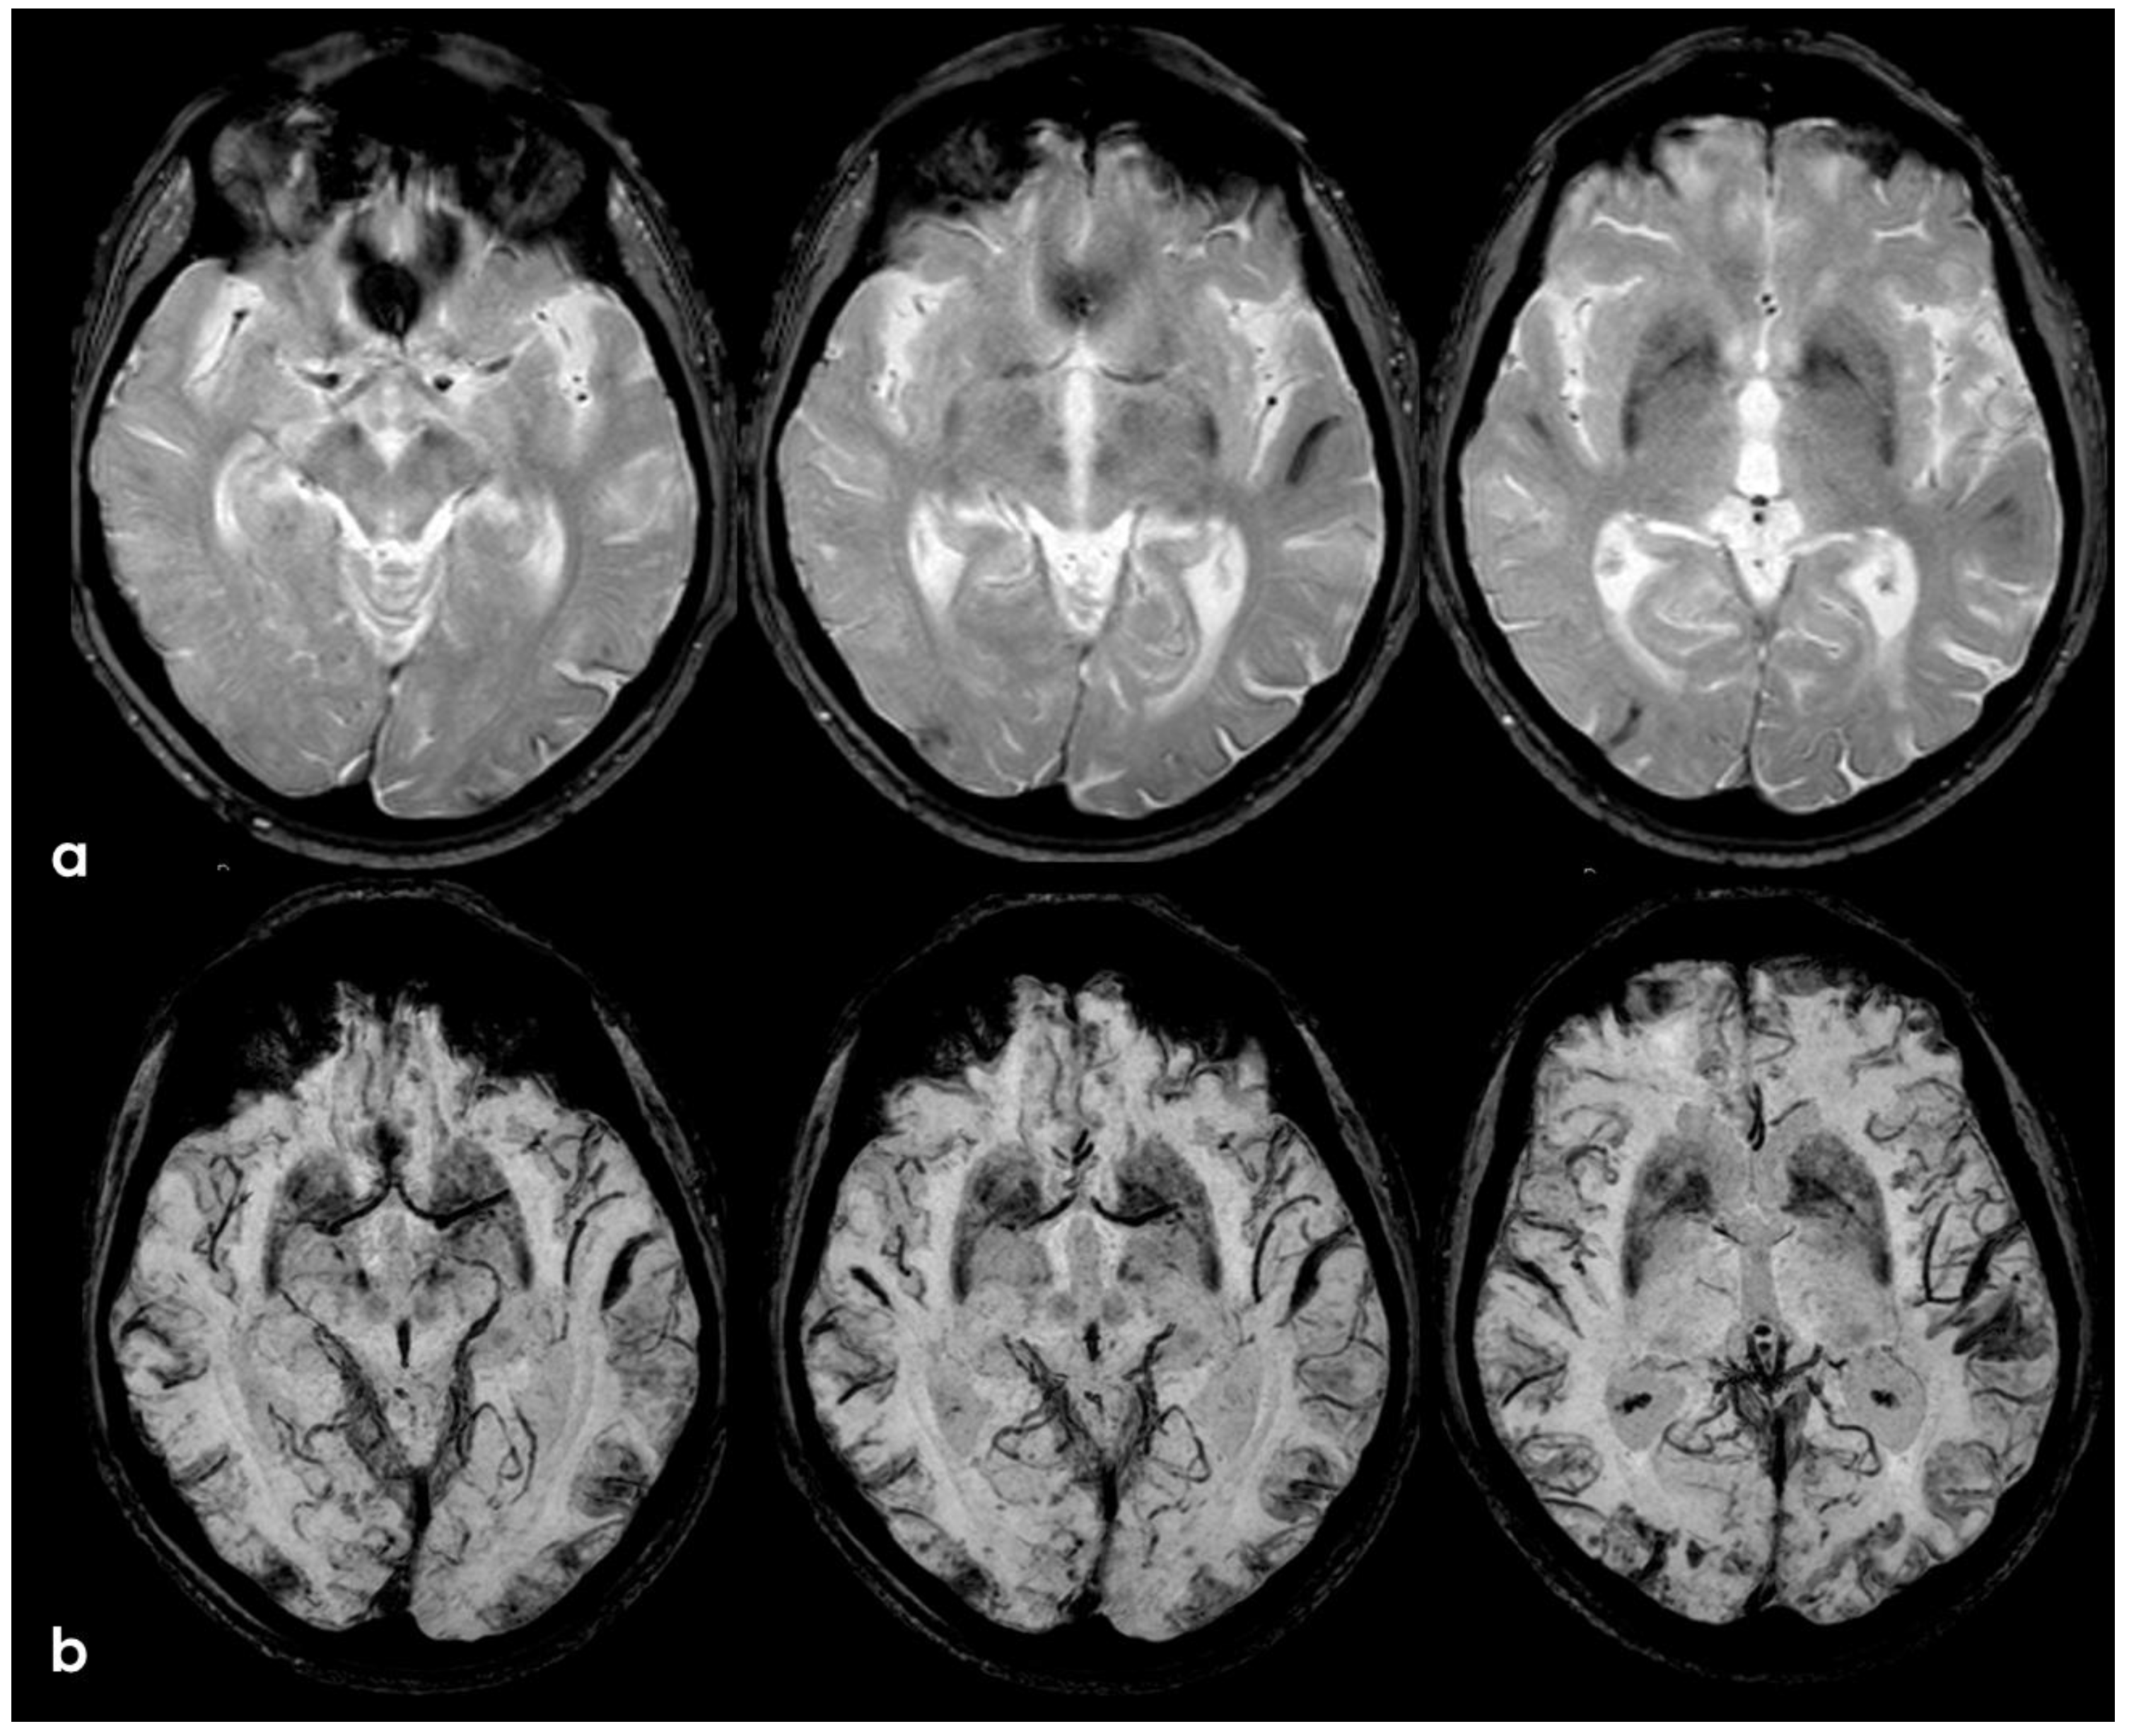

2. December 2013: Sulcal SAH and TFNEs

6. December 2017: Recurrent SAH

9. Additional Information and Discussion: How This Case Helps to Better Understand CAA